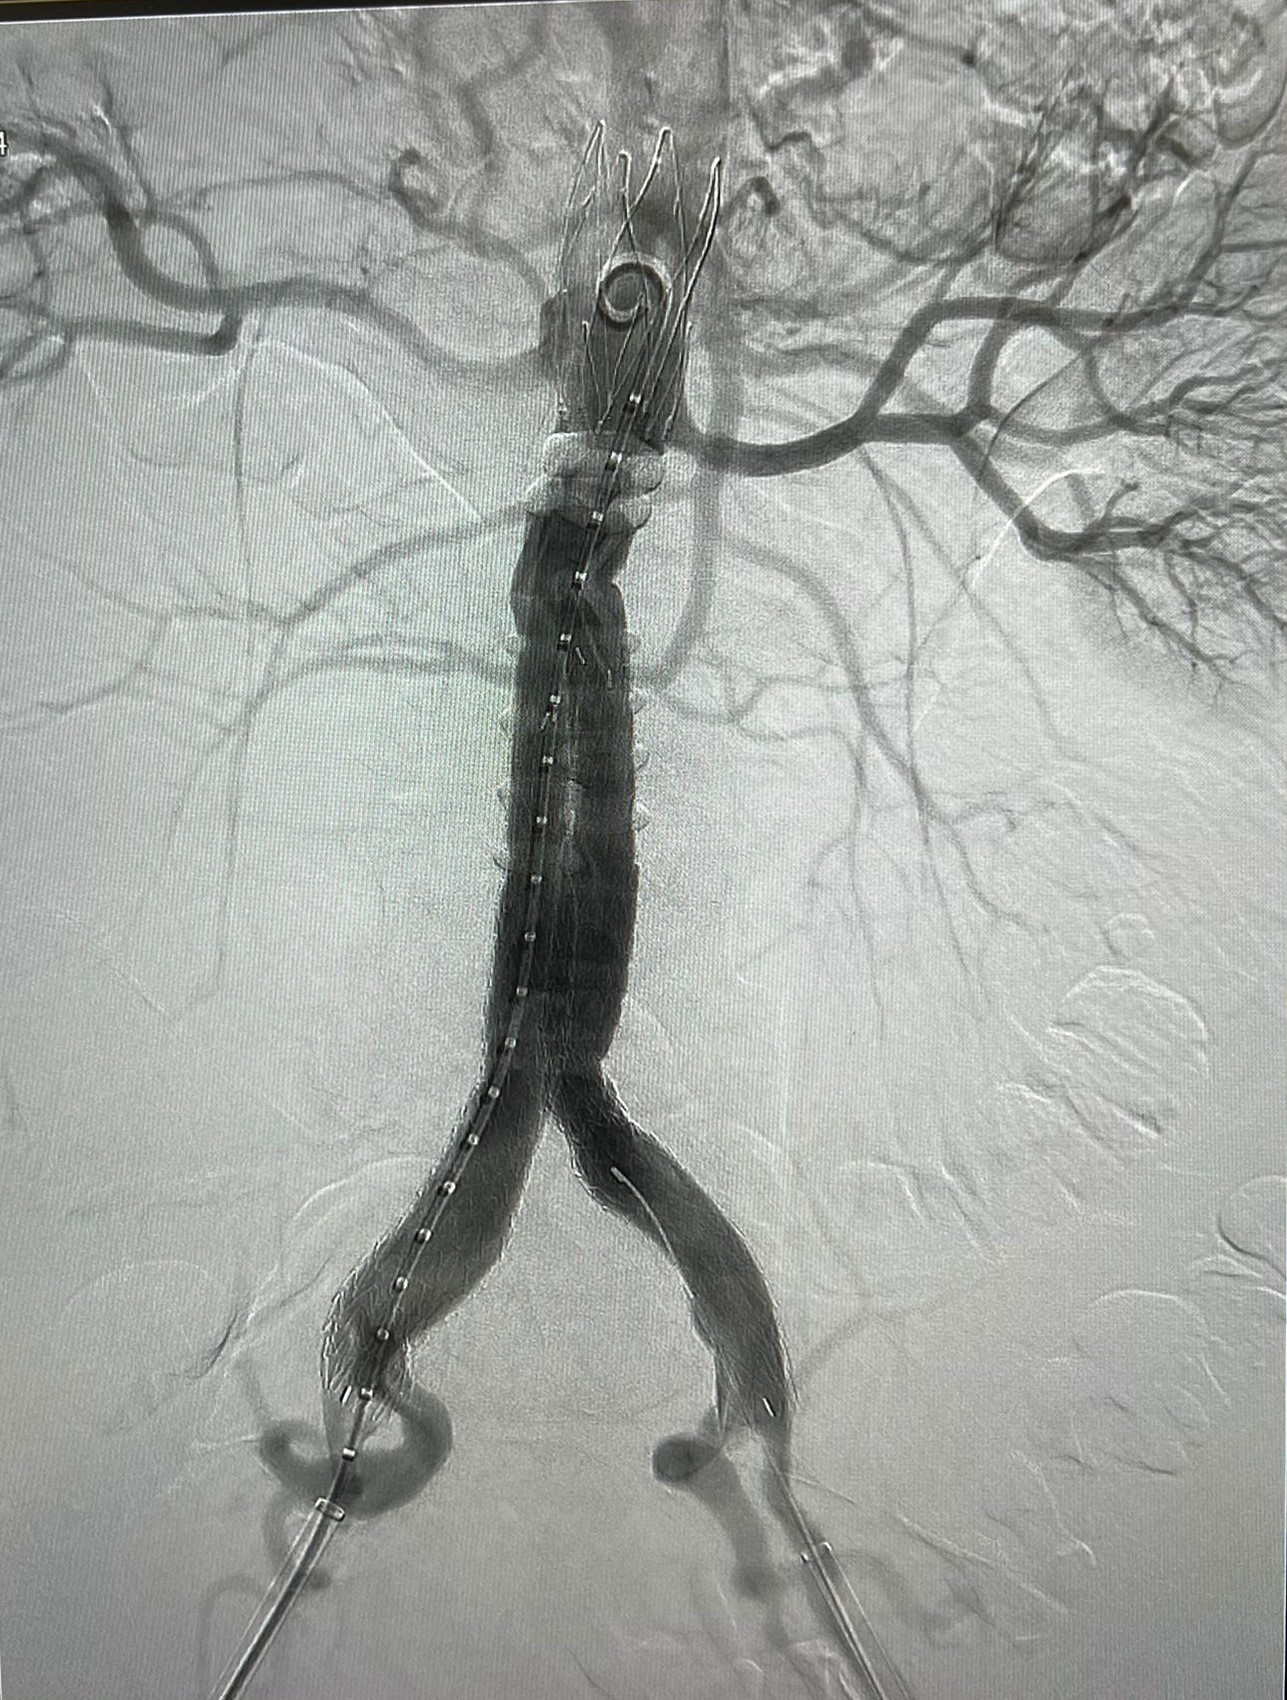

În Clinica de Chirurgie Cardiovasculară a UMF Carol Davila de la Spitalul Clinic de Urgență București (Floreasca) au fost rezolvate săptămâna trecută trei cazuri de anevrism de aortă abdominală infrarenală, dintre care unul rupt.

Soluția adoptată a fost non-chirurgicală: s-a realizat implantarea unor stentgrafturi endoaortice pecutanat (fără incizii chirurgicale) – EVAR, se arată pe pagina de Facebook Chirurgie cardiovasculară Floreasca.

Procedurile au fost realizate de prof. univ. dr. habil. Horațiu Moldovan (foto), Șeful Clinicii de Chirurgie Cardiovasculară, împreună cu colegii chirurgi, cardiologi intervenționali și anesteziști: